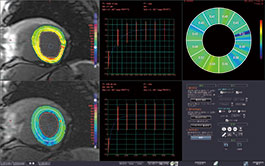

MR MYOCARDIAL T1 MAPPING

Using MR heart data scanned with and without a contrast material with different TI, this protocol extracts inner and outer wall contours of LV, shows color maps of T1 values calculated from T1 relaxation curve, and shows ECV calculated from hematocrit values and blood T1 values.